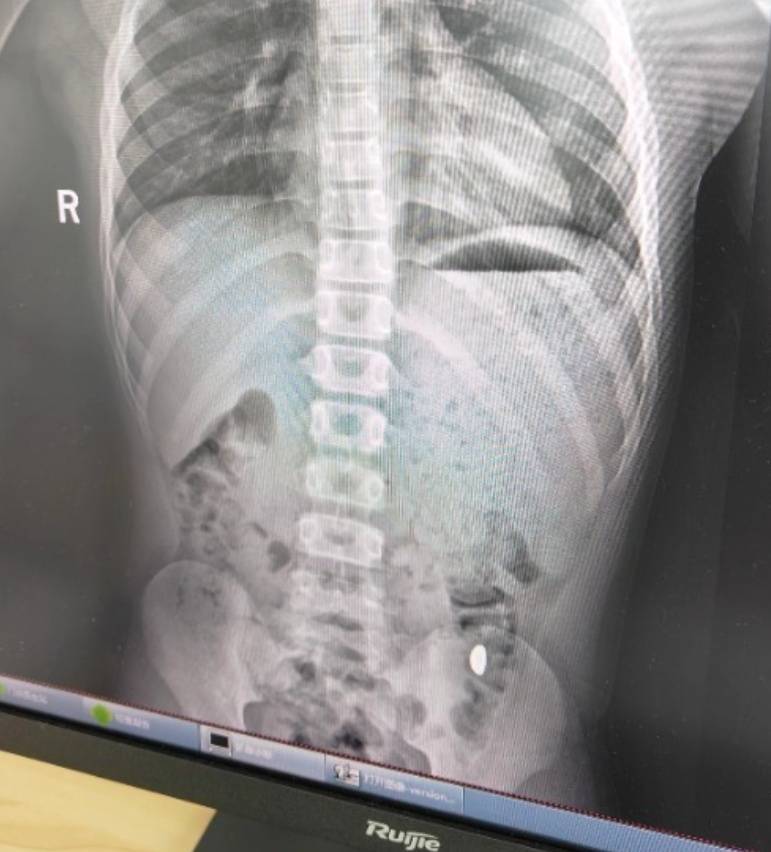

右下加亮点为金豆老币兑换价格表

纪女士说,她起初以为儿子在开玩笑,当确认儿子真的吞了金豆子时,她也是哭笑不得老币兑换价格表。“我每天都提醒他不能在外面拉屎,这个屎有点贵。”纪女士说,她等了5天,对着大便扒拉了两次还是没有找到金子,于是10月26日,她就带儿子去了医院。“上午去的医院下午就拉出来了。”纪女士说。